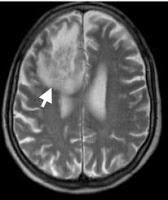

Es una colección de líquido purulento que se forma entre el cerebro y las meninges como consecuencia de una infección en un punto concreto del mismo que supura, es decir, que desprende material infeccioso mezclado con células defensivas. La infección, al igual que en la meningitis, viene directamente desde la sangre o de un punto infectado en otra zona de la cabeza, especialmente desde los senos paranasales, los oídos y la boca, rara vez es una complicación de la meningitis. Es una enfermedad en general poco frecuente, que puede aparecer a cualquier edad, aunque predomina en los adultos jóvenes y sobre todo en el sexo masculino.

Si no se detecta y se trata a tiempo puede conducir a la muerte en muchos casos. Gracias al escáner, hoy en día cabe la posibilidad de hacer un diagnóstico rápido, pese a lo cual el riesgo de fallecimiento y de producirse secuelas neurológicas es bastante alto.